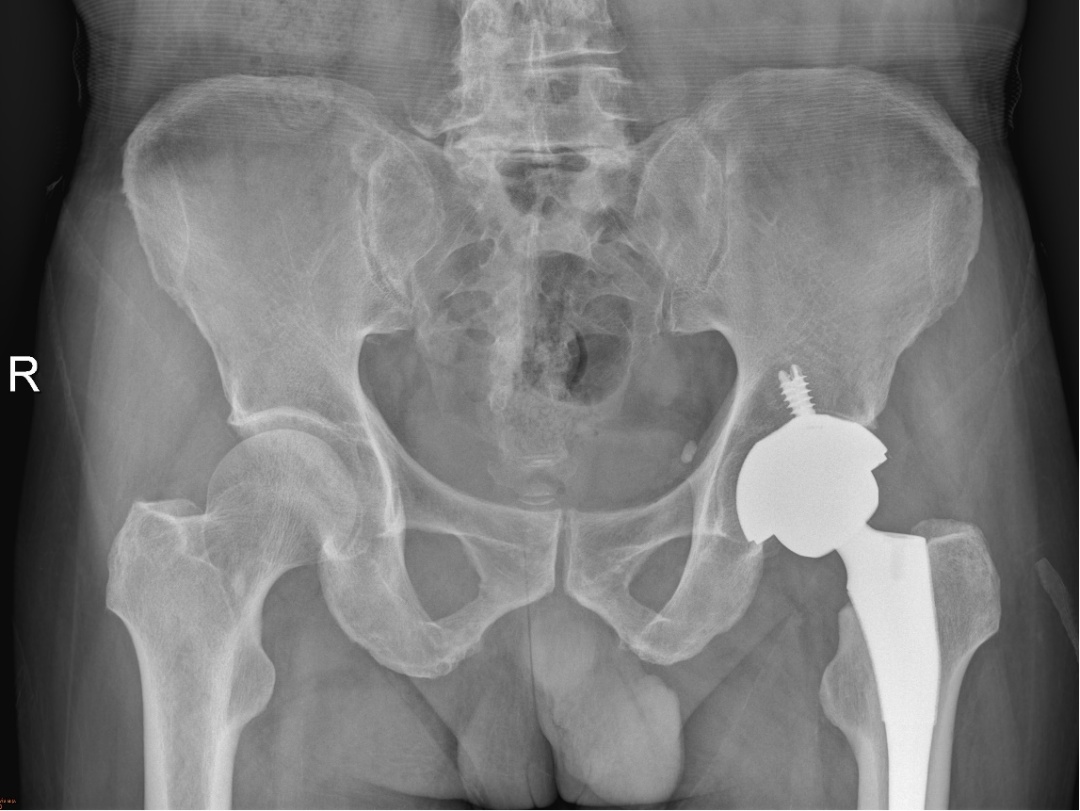

(术后第六周复查骨盆X片)

术后第六周,铁山再次来到何川诊室复诊,已经身形矫健、行走自如了。